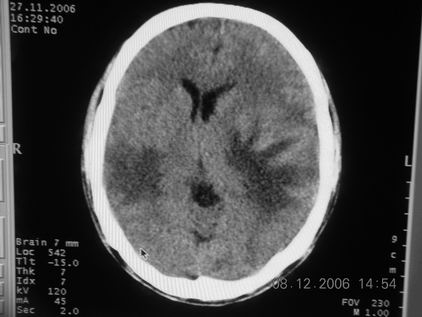

标题: CT11164:男,46岁,白血病患者,,大家看看. [打印本页]

标题: CT11164:男,46岁,白血病患者,,大家看看.

以前的片子,病史忘了,男,46岁,白血病患者,后来到中山二院诊断为

谁见过白血病中枢系统改变是怎么样的吗?

白血病脑浸润。

支持白血病脑浸润.

1 多发脑脓肿可能性大.>2 白血病浸润.

白血病脑浸润。没见过!但结合病史应首先考虑此病。

支持白血病脑浸润

结合病史考虑白血病脑浸润。

结合白血病病史,支持考虑白血病脑浸润。

结合病史考虑白血病脑浸润